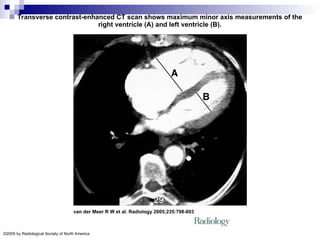

Transverse contrast-enhanced CT scan shows maximum minor axis measurements of the

right ventricle (A) and left ventricle (B).

Transverse contrast-enhanced CTscan shows maximum minor axis measurements of the right ventricle (A) and left ventricle (B). van der Meer R W et al. Radiology 2005;235:798-803 ©2005 by Radiological Society of North America

• #33 Figure 1. Transverse contrast-enhanced CT scan shows maximum minor axis measurements of the right ventricle (A) and left ventricle (B). Note the flattening of the interventricular septum. RV/LV ratio = 1.81.